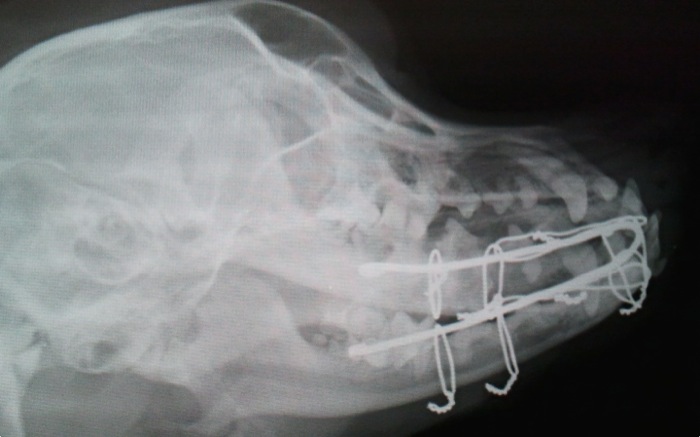

Se realiza una fijación externa con una única aguja de Kirshner de 2 mm por aposición a la cara medial de incisivos, caninos y primer molar. Ésta se moldea hasta conseguir una adaptación ajustada y queda como elemento de fijación de manera temporal a los dientes para corregir las anomalías de posición dental y ósea.

La aguja de Kirshner una vez queda en su forma y posición definitiva se sujeta con alambre de 0,8 mm primeramente en rostral cruzando sobre ambos caninos. El cierre se hace bajo el mentón como en la típica fractura de sínfisis que tanto vemos en el gáto paracaidista.

Los distintos cerclajes se aprietan simultáneamente y entierran por último casi en su totalidad bajo la mucosa. Antes habían sido introducidos paralelamente a las ramas mandibulares bajo esta mucosa pero pasando por encima de la aguja de Kirshner.

Una vez apretado todo se vuelve a confirmar el cierre y correcta aposición de todas la piezas dentales. Al quedar los incisivos superiores proximalmente nos da una buena oclusión.

La radiografía permite ver la adaptación de todos los elementos de fijación. Tan solo nos queda ver la evolución a corto plazo y valorar cualquier molestia o roce a nivel de la boca o lengua.